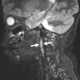

Enlarged lateral retropharyngeal lymph node